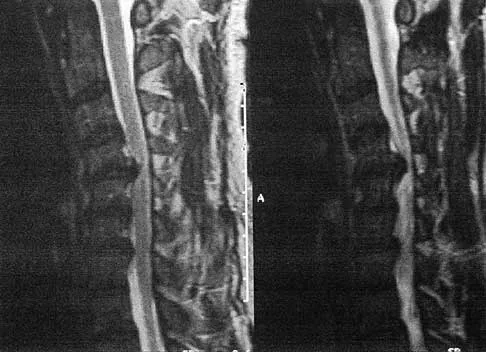

A 21-year-old man has had posterior neck discomfort for the past 6 months. Radiographs, an MRI scan, and a photomicrograph of the biopsy specimen are shown in Figures 17a through 17d. What is the most likely diagnosis?

Explanation